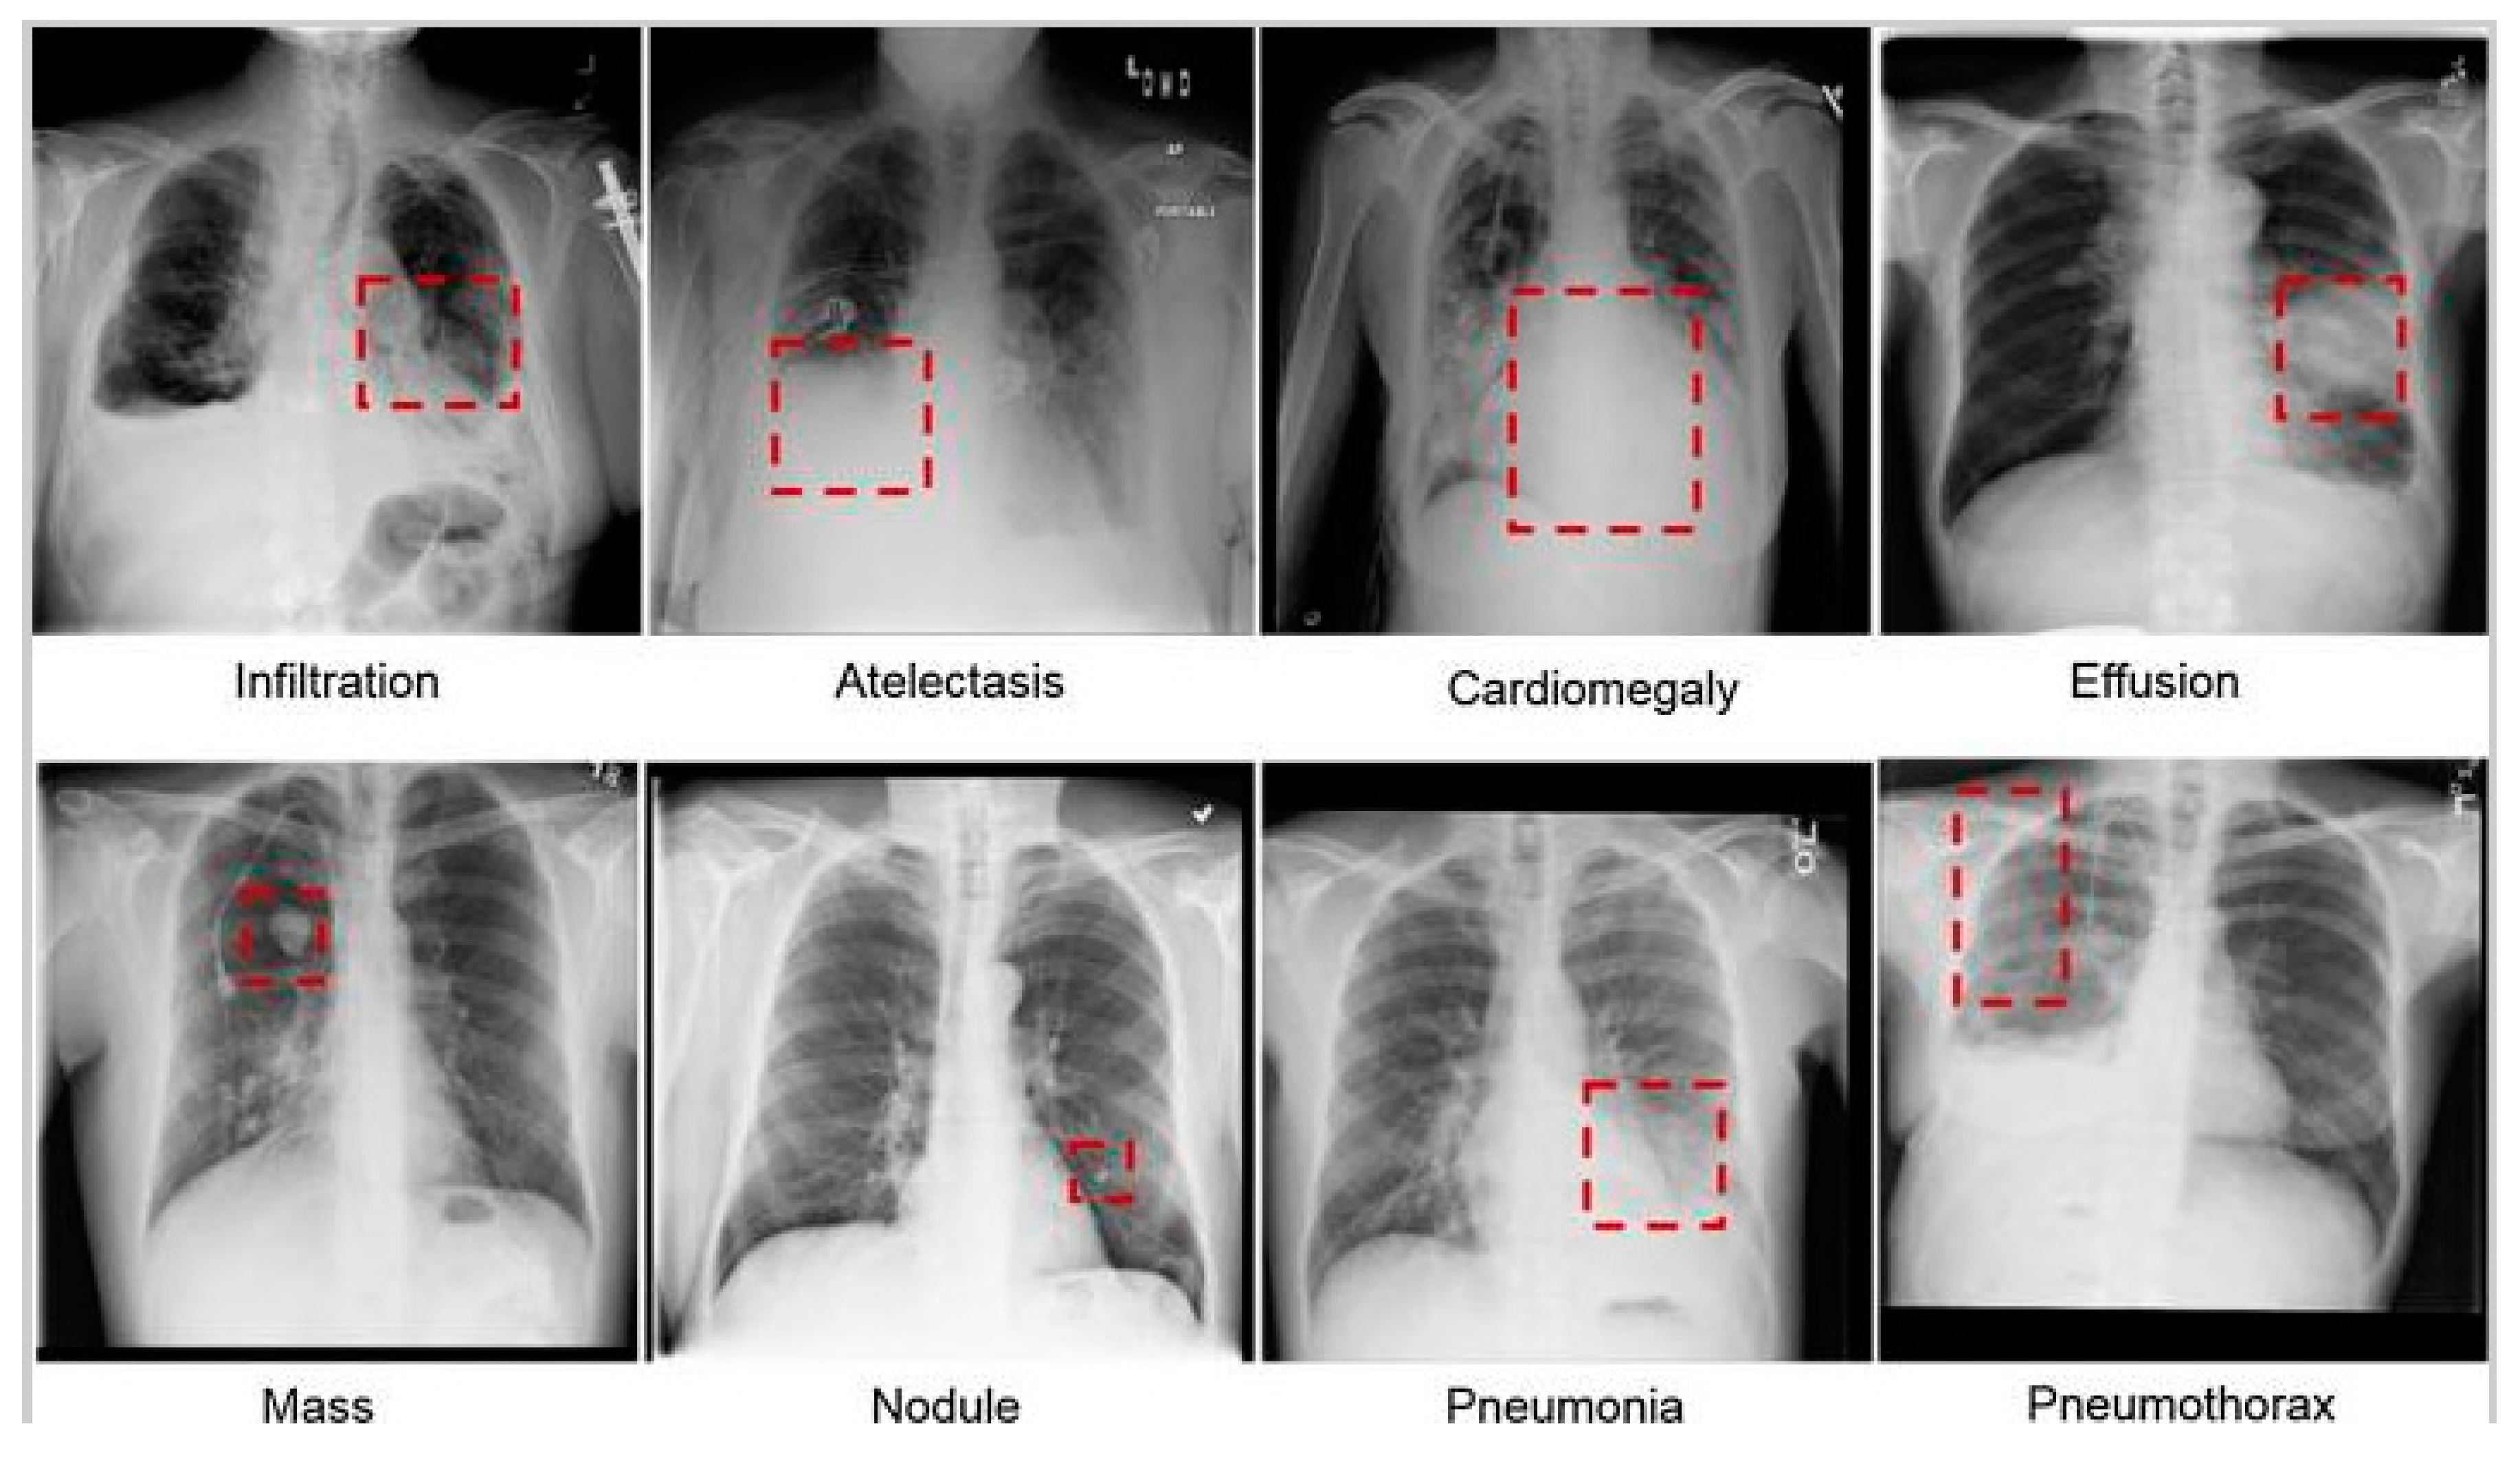

- Diverse Types of Abnormalities